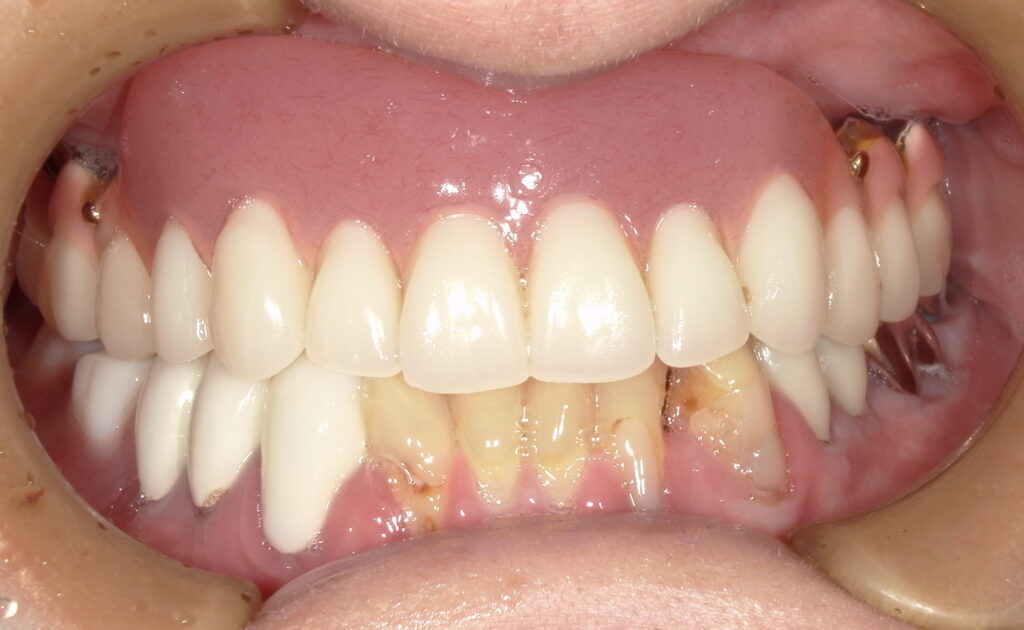

治療前のご様子

お口の中を拝見すると、上顎は歯を残すことができず、総入れ歯。

下顎には数本残せる歯があり、レジリエンツテレスコープを用いた治療を行うことになりました。